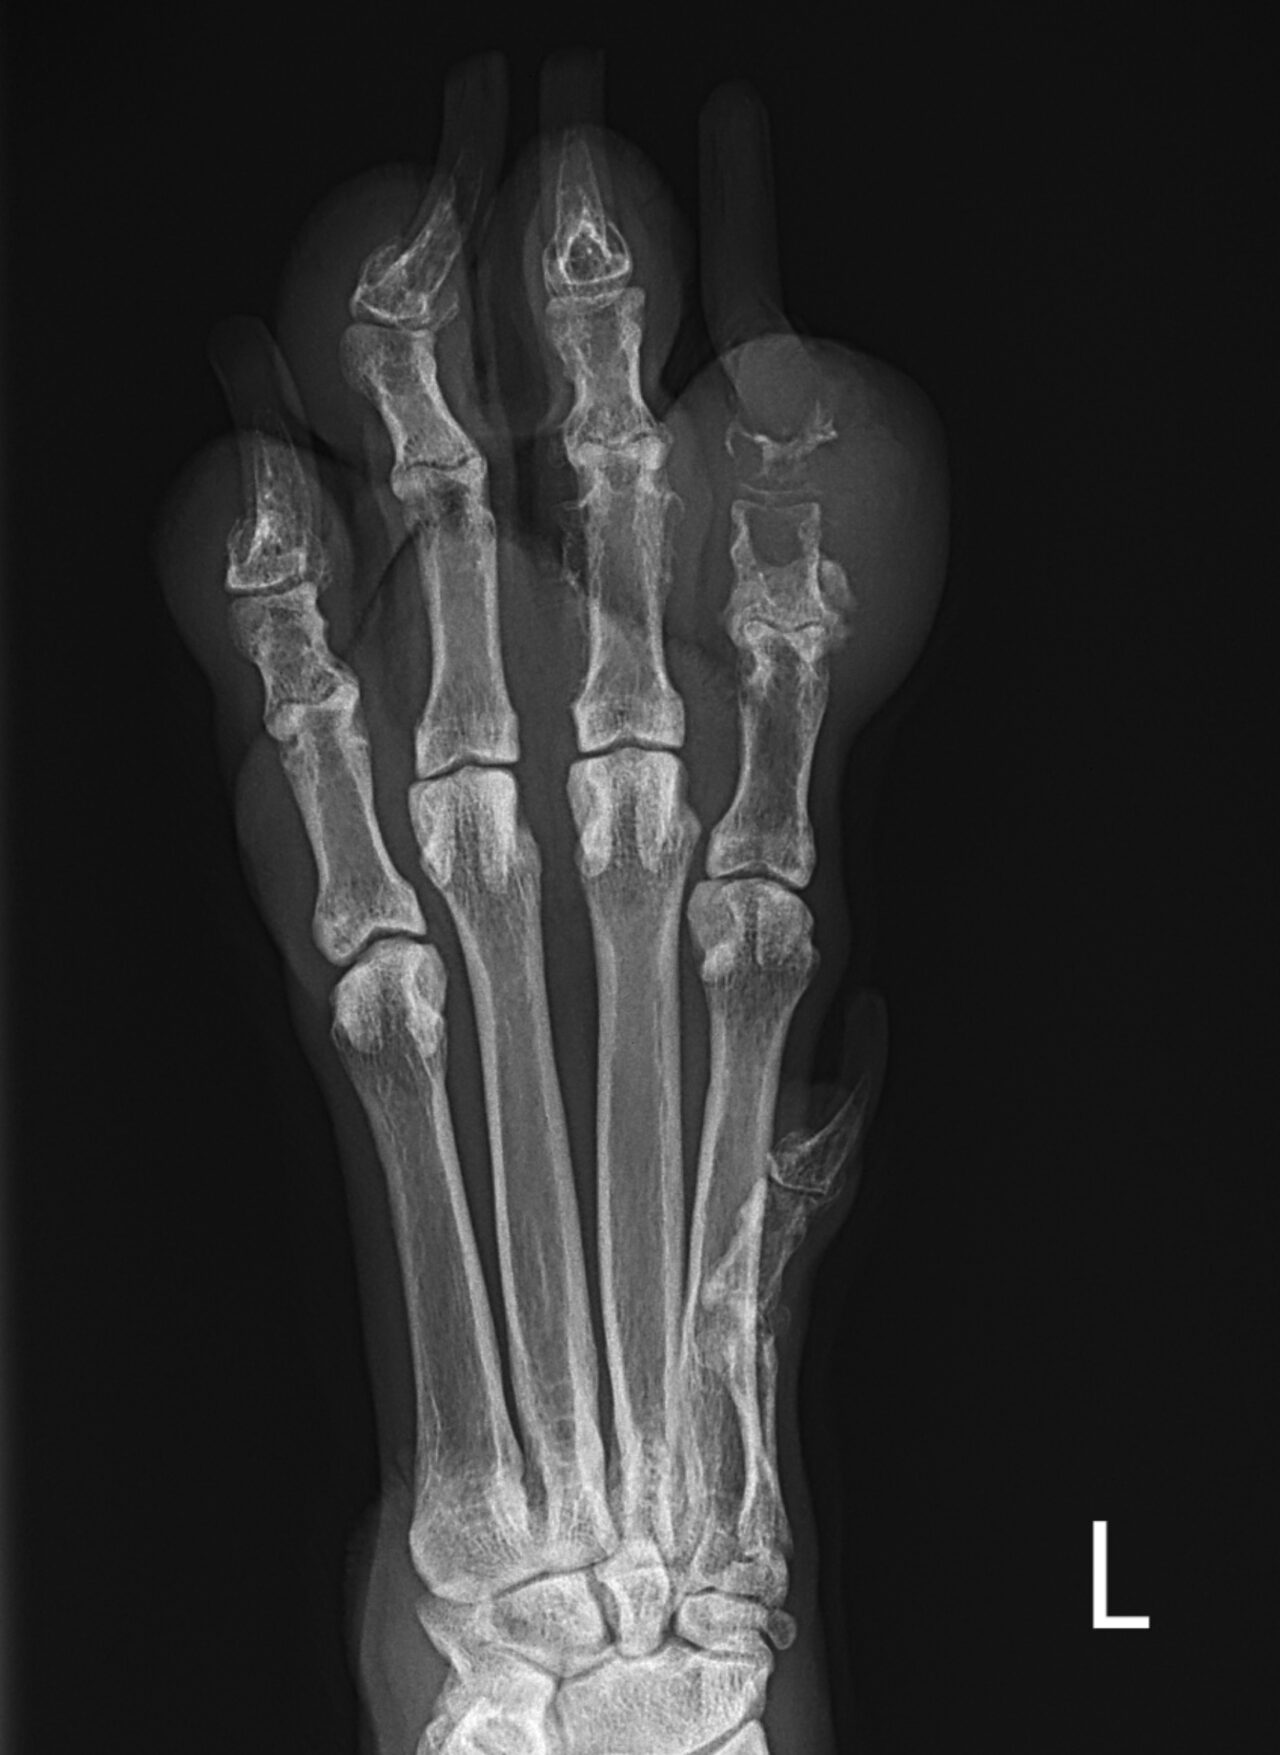

爪床腫瘍(扁平上皮癌) 高齢のラブラドールレトリバーが爪の根元が腫れてびっこを引いているとのことで紹介来院しました。X線検査では既に骨が溶けており、悪性腫瘍が示唆されます。細胞診で扁平上皮癌の疑いとなったため翌日に手術(断指)を行いました。 症例カテゴリー 放射線治療整形外科軟部組織外科脳神経外科内科腫瘍外科救急・集中治療リハビリテーション科腫瘍内科内視鏡科脳神経科呼吸器外科中医・漢方猫の腎移植循環器科